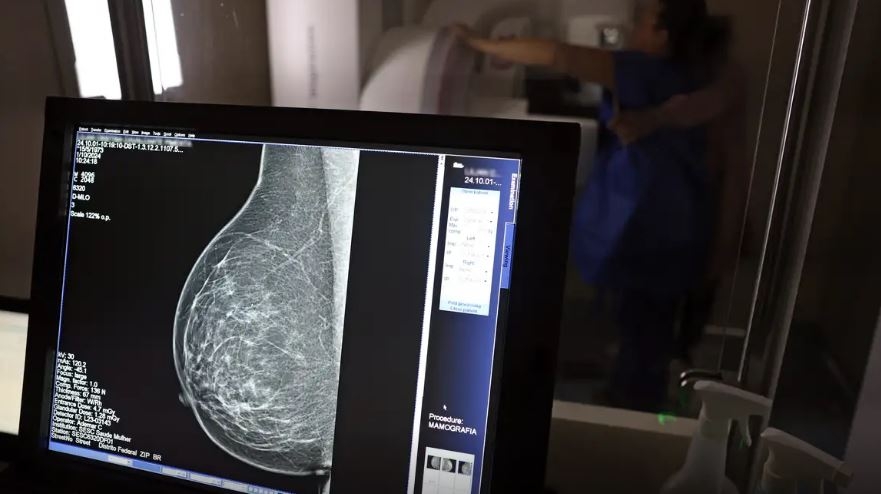

No mês de conscientização sobre o câncer de mama, um relatório destaca a importância de acesso igualitário ao rastreamento e tratamento da doença. Segundo o Atlas da Radiologia no Brasil, do Colégio Brasileiro de Radiologia e Diagnóstico por Imagem (CBR), o acesso aos mamógrafos ainda é um desafio.

O país tem 6.826 equipamentos registrados, sendo 96% em funcionamento. Metade deles está disponível no Sistema Único de Saúde (SUS), responsável por atender 75% da população. Isso equivale a 2,13 mamógrafos por 100 mil habitantes dependentes do SUS.

Na saúde suplementar, que cobre 25% da população, o cenário é mais favorável: 6,54 aparelhos por 100 mil beneficiárias, quase o triplo da rede pública. O Acre exemplifica essa disparidade — são 35,38 mamógrafos por 100 mil habitantes na rede privada, contra 0,84 no SUS.

O Brasil tem uma cobertura muito baixa de mamografias: 24%. O ideal recomendado pela Organização Mundial da Saúde é de 70%. Mesmo em lugares como o estado de São Paulo, que tem a maior concentração de mamógrafos do país, a taxa gira em torno de 26%.